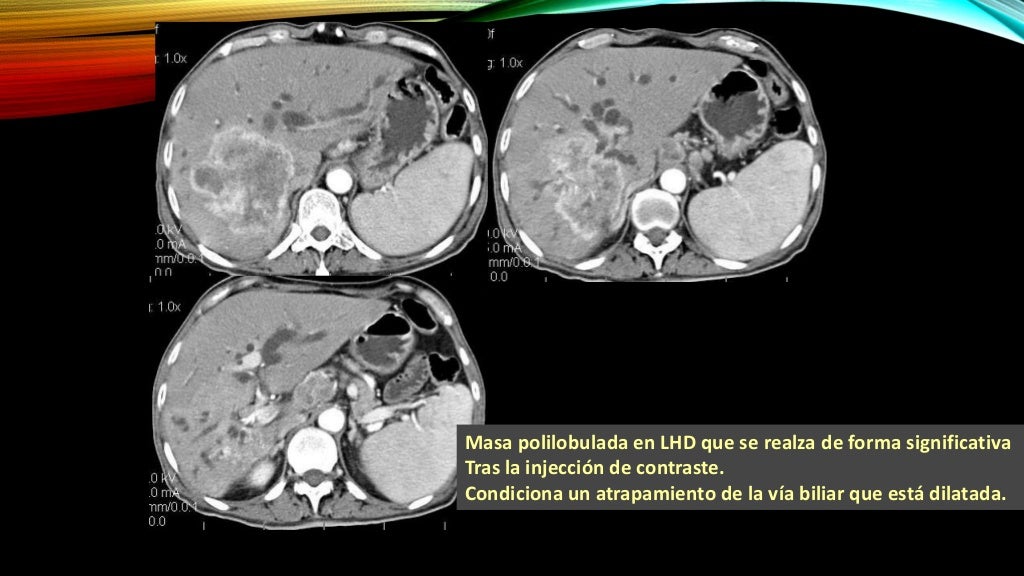

Colangiocarcinoma intrahepatico

atomografía abdominal (año 2011) se observan dos masas en hígado